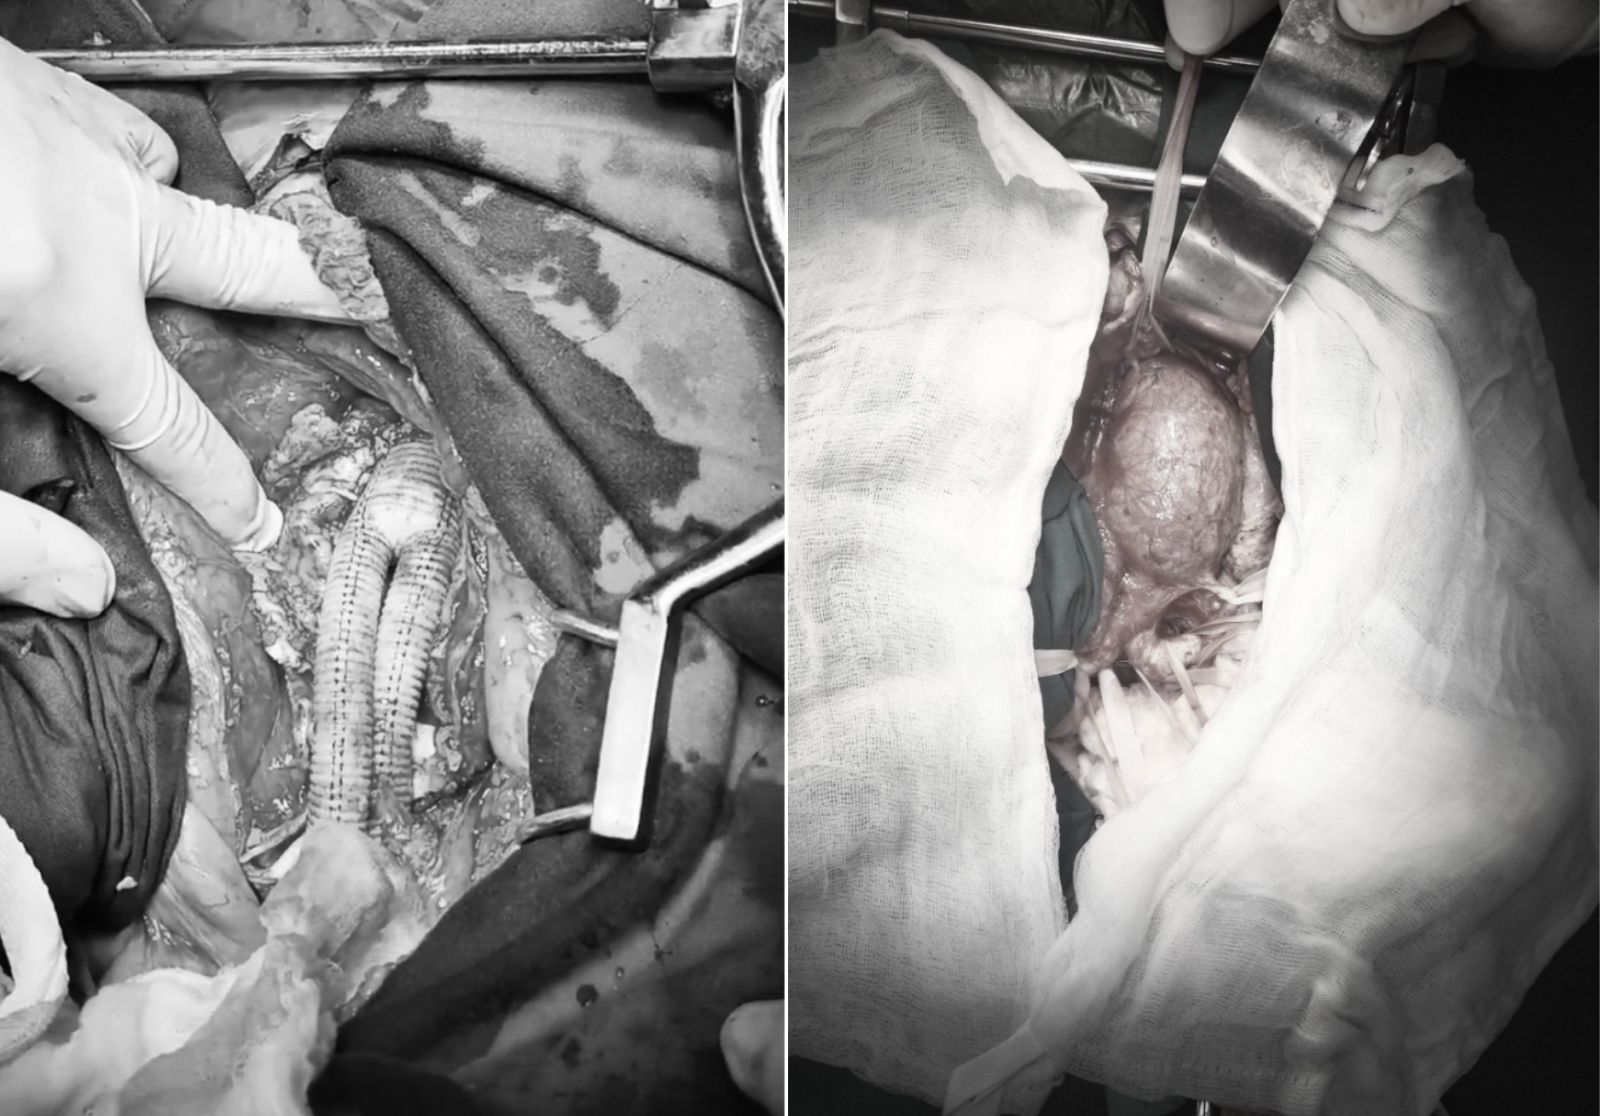

Ekip mổ thay mạch nhân tạo cho bệnh nhân phình động mạch chủ bụng, hai động mạch chậu chung.

Huyết áp và các thông số máu được kiểm soát tốt cho đến thời điểm phẫu thuật. Phẫu thuật được thực hiện ngày 12/7 với kỹ thuật thay đoạn động mạch chủ bụng và chậu chung 2 bên bằng động mạch nhân tạo hình Y.

Ca phẫu thuật diễn ra theo kế hoạch, túi phình động mạch chủ bụng của bệnh nhân được loại bỏ và được thay thế bằng đoạn mạch nhân tạo. Bệnh nhân hồi phục ổn định và nhanh sau phẫu thuật.

Đoạn mạch nhân tạo được thay vào và khối phình động mạch chủ bụng dưới thận được loại bỏ.